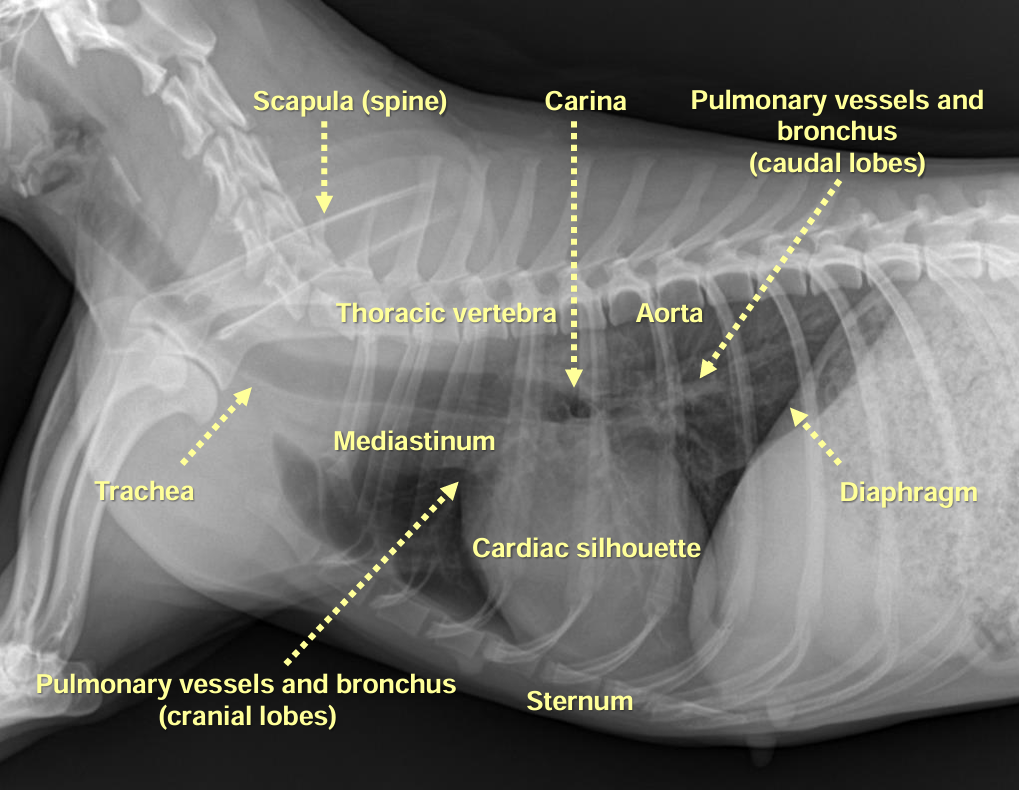

1. Normal Anatomy

| Thorax | |